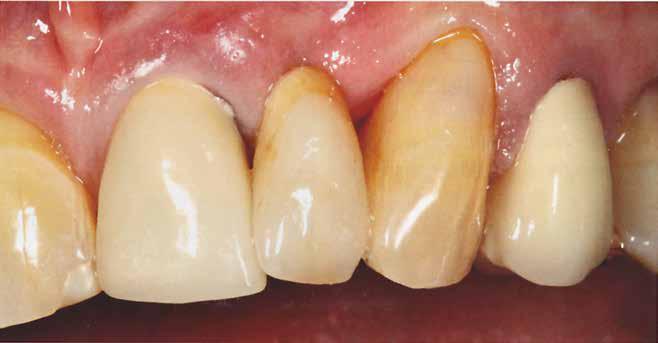

2015-ben egy 47 éves férfi páciens állkapocs-ízületi panaszai miatt kereste fel a rendelőnket. Ezen felül esztétikai problémát jelentett számára, hogy az egyik felső nagymetszőfogán lévő héj eltört (1-3. ábrák). A klinikai és radiológiai vizsgálatot követően megállapítható volt, hogy a páciens kifejezett bruxizmusa miatt csökkent a harapási magassága, és jelentős mennyiségű saját foganyagot abradált el (4. ábra)

A páciens a megkezdett kezelések folytatása miatt 2017ben ismét felkereste a rendelőnket (7. ábra). Ekkor egy új intraorális lenyomatvétel történt (Carestream 3600).

A fogak preparálásához egy új mock-upot készítettünk háromdimenziós nyomtató segítségével (SolFlex, VOCO) bisz-akrilátból (Structur 3). A mock-up elkészítéséhez felhasznált sablont vákuum technológia segítségével hoztuk létre (V-Print ortho, VOCO). A mock-up felhelyezését követően a páciens fogait minimál invazív módon készítettük elő (8. ábra).

A már előzetesen preparált felső frontfogak csiszolt csonkjainak megtartottuk az eredeti formáját. Az alsó és felső őrlőfogak preparációja nem volt szükséges (1.7-1.4, 2.4-2.7, 3.7-3.4, 4.4-4.7), az alsó kismetsző fogakat minimál invazív módon készítettük elő. Az előkészítést követően új digitális lenyomat készült. Az így kapott digitális adatokat továbbítottuk a fogtechnikai laboratóriumba (9. ábra). A virtuális modellt ezek alapján hozták létre (AnatomicLab), és a minta elkészítéséhez szükséges STL fájlt továbbították egy háromdimenziós nyomtatóra (SolFlex 650, VOCO), amely segítségével elkészítették az új mintát (V-Print model, VOCO).